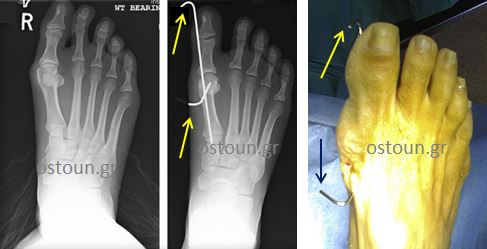

Στις διαδερμικές επεμβάσεις 1ης γενιάς για το κότσι χρησιμοποιήθηκαν βελόνες για τη συγκράτηση της διόρθωσης. Πέραν της αντιαισθητικής εικόνας με τις βελόνες να προεξέχουν έξω από το δέρμα (ώστε να αφαιρούνται εύκολα 4 εβδομάδες μετά την επέμβαση), υπήρξαν και τα ακόλουθα προβλήματα:

- Οι βελόνες παρείχαν μια μάλλον πενιχρή συγκράτηση της οστεοτομίας, με κίνδυνο απώλειας της ανάταξης και υποτροπή της παραμόρφωσης.

- Προκαλούσαν συχνά λοιμώξεις κατά την είσοδο μικροβίων δια της βελόνας (pin-track infection).

- Απαγορευόταν η πρώιμη φόρτιση, επομένως και η βάδιση μετεγχειρητικά.

Διαδερμική τεχνική 1ης γενιάς με τις βελόνες που προεξείχαν του δέρματος